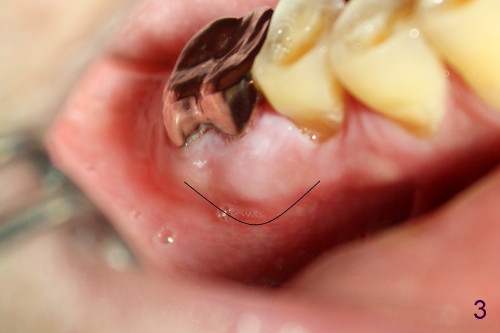

如以前介绍()右下第一磨牙近中根尖阴影根管治疗后逐渐增大(图一*),最后病人同意做根切,术前颊侧观显示近中根尖处肿胀(图二*),前庭沟挺深的,暴露可能不错(金杭晴理论),但如何做切口呢?根尖附近半月形切口(图三),还是牙龈沟切口附加斜形切口(图四)?结果

Probably due to our similar background (oral surgery), I chose surgical mode. I particularly like your idea: 根切的关键在于前庭沟浅还是深,深好做,因为暴露好。In fact the vestibule is deep in this case as will be shown soon in my web. What incision should I make, gingival sulcus or apical semilunar, for the best exposure? Xin Fri, 3 May 2013 18:22

Dear Dr. Wei: 我喜欢gingival sulcus incision, apical semilunar 视野太小。我不会生气的,只不过和方老师开个玩笑。等看你的照片。请告知你们的阿拉斯加旅行计划,看我们能不能一起去。很愿意与你交流,因为你的"open, frank & even"。杭晴 Friday, May 3, 2013 11:49 PM